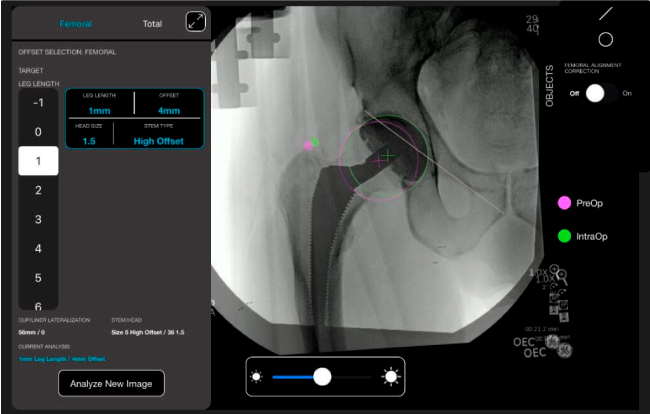

Nuestro sistema de navegación digital VELYS HIP NAVIGATION ™ para cirugía de cadera, es una tecnología innovadora y no invasiva diseñada para apoyar la toma de decisiones de los médicos en tiempo real y basada en datos; aumentando la precisión y dando mejores resultados.

Nuestro navegador de cadera VELYS HIP NAVIGATION ™ es una solución digital que te acompañará a mejorar cada paso de las fases operatorias.

El sistema de navegación digital VELYS HIP NAVIGATION ™ para cirugía de cadera, es una tecnología innovadora y no invasiva diseñada para potencializar la toma de decisiones en tiempo real y basada en datos; aumentando la precisión y mejorando los resultados a corto, mediano y largo plazo para los pacientes.

Planeación preoperatoria mediante la creación de plantillas digitales para reemplazo de cadera y análisis intraoperatorio

Datos procesables en tiempo real para la toma de decisiones.

Desplazamiento y offset para posicionamiento óptimo del componente (vástago) femoral.

Anotaciones digitales y herramientas de análisis de longitud de pierna.

Con tecnología ONETRIAL® que calcula automáticamente el cambio en la longitud de la pierna y el desplazamiento para todas las combinaciones de implantes en una tabla fácil de leer.